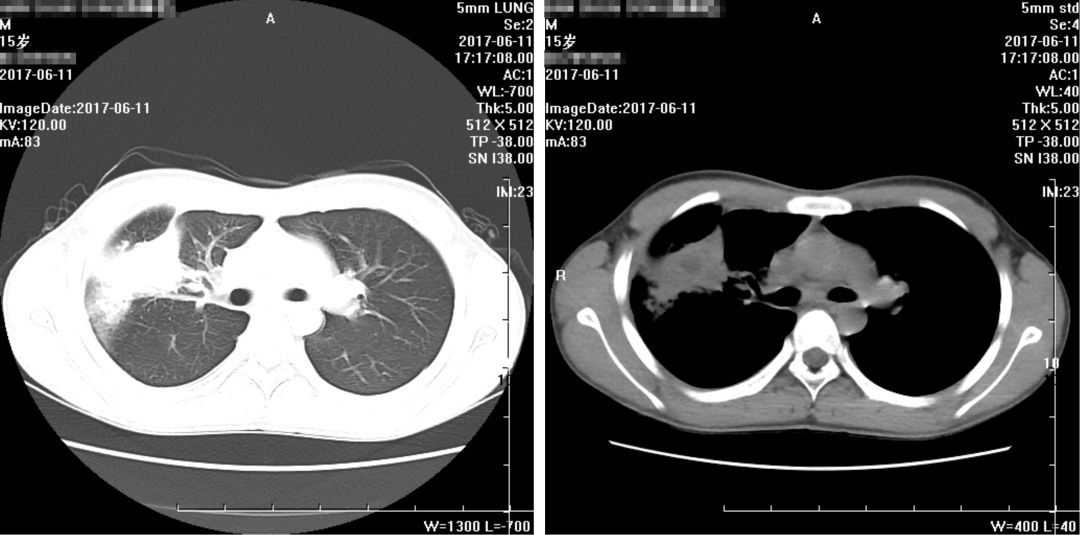

(2017年6月11日)

(2017年6月22日)

入院CT报告(2017-06-11):

1、右肺上叶-中叶见团块状软组织密度影,周边可见磨玻璃密度影,病变大小约5.08*3.38cm,CT值约25HU,其内密度不均,中心可见低密度影,CT值约5HU,病变与胸膜宽基底相连,与右侧横膈胸膜分界不清,建议增强进一步检查。

2、右肺上叶前段支气管欠通畅,建议复查。

3、右肺上叶、中叶、下叶内基底段条索

4、右侧胸膜增厚,右侧少许胸腔积液

5、纵隔内、两侧腋窝下小淋巴结,前纵隔软组织密度影,考虑未退化完全胸腺组织。

复查胸部CT报告:

1、右肺病变较前略有变化,部分减轻,尖段病变增多,请结合病原学检查;

2、右侧少许胸腔积液基本吸收;

3、纵隔及两侧腋窝多发淋巴结部分稍增大,较前未见明显变化。

余大致同前。